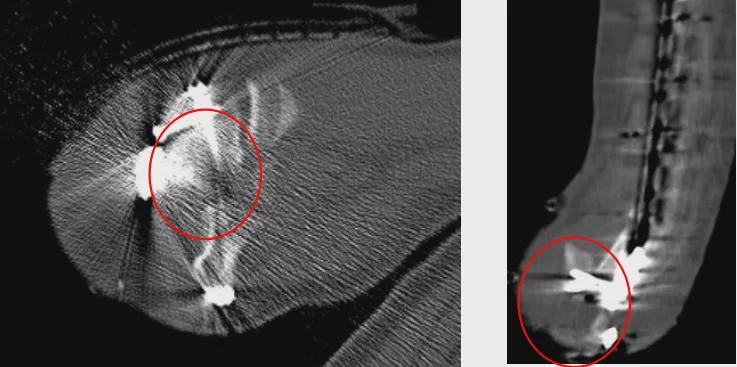

(术后一个月,CT显示骨折复位情况)

肱骨远端C3型骨折

部分骨质缺损